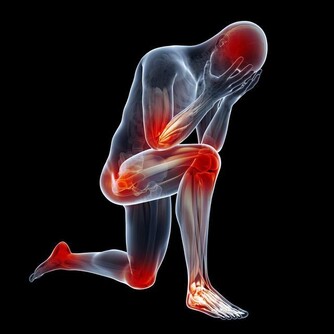

4、兩腿麻木無力、活動減少、腿腳冰涼、晚上疼醒:

要考慮下肢動脈硬化閉塞。

這點常常因為老人家覺得不重要不和子女說,會被忽視,拖到了腳壞死了才來就診,治療難度大,效果大打折扣。